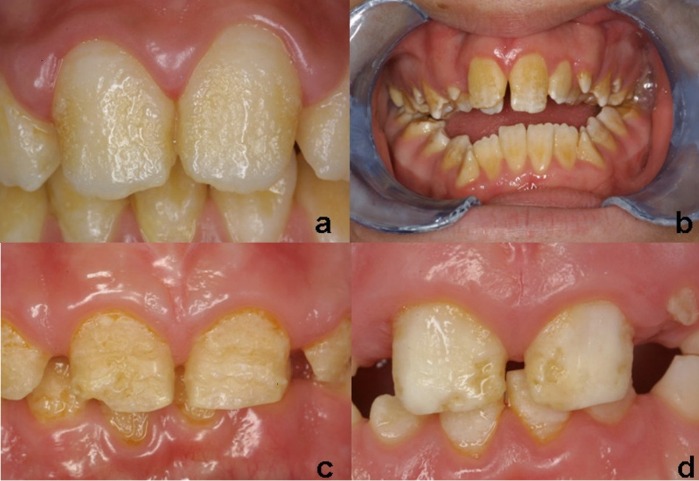

Диагностика. Выборка для исследования состояла из 12 пациентов (5 мальчиков и 7 девочек) в возрасте от 4 до 17 лет (10.6±4.6 лет) на момент обращения. Во всех случаях имелся доступ к семейному анамнезу. Наличие схожих дефектов развития эмали у членов семьи было подтверждено у 9 пациентов. У 8/12 пациентов была диагностирована гипопластическая форма AI, в 2/12 случаев была отмечена гипоматурация и в 2/12 случаев гипокальцификация. Жалобы пациентов в основном сводились к неудовлетворительной эстетике и повышенной чувствительности зубов. Состояние здоровья полости рта пациентов на момент начала исследования суммировано в таблице № 1. У 8 пациентов наблюдался активный кариес (рис. 1).

Рис. 1. Снимок полости рта пациента, страдающего amelogenesis imperfecta и демонстрирующего высокую кариозную активность.

- Гипопластическая форма (рис.1)

Имеются количественные изменения в процессе формирования матрицы. То есть, эмаль правильно сформировалась, но она имеет недостаточную толщину. Эта форма наследуются аутосомно-доминантно/рецессивно и Х-сцепленно. Поражённые участки эмали чаще локализованы на вестибулярной (щёчной) поверхности зубов. Видны ямки (или овальные углубления) различных размеров и глубины, бороздки различной протяжённости, имеющие продольное направление. Эмаль достаточно твердая, и её поверхность может быть гладкой, шероховатой, гранулообразной, но непоражённые участки сохраняют свой блеск. Стоит отметить, что глубина дефекта определяет интенсивность окраски эмали (чем глубже дефект, тем интенсивнее окрашивается истонченная эмаль и обнажённый дентин). Эмаль становится светло-желтой или светло-коричневой. Наблюдается гиперестезия (на холод и горячее), скол эмали, уменьшение величины зуба, тремы между зубами (не всегда). Гипопластическая форма встречается чаще остальных форм НА (61,2 %)

Рисунок 1 | Гипопластическая форма

Рисунок 2 | Гипоматурационная форма

Рисунок 3 | Гипоминерализованная форма